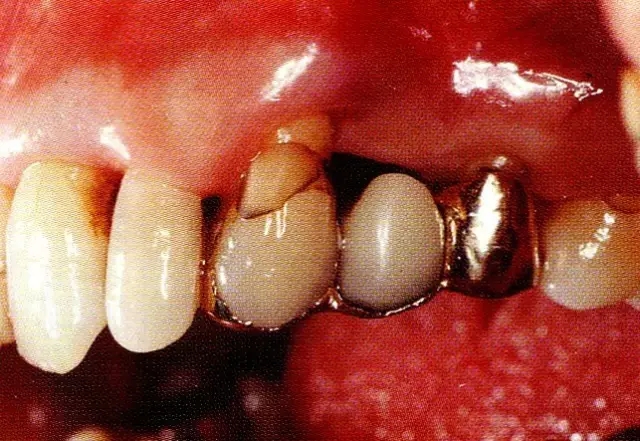

▲圖8-1  52歲,上班族,女性。來院主訴是左上橋體下部有空隙。